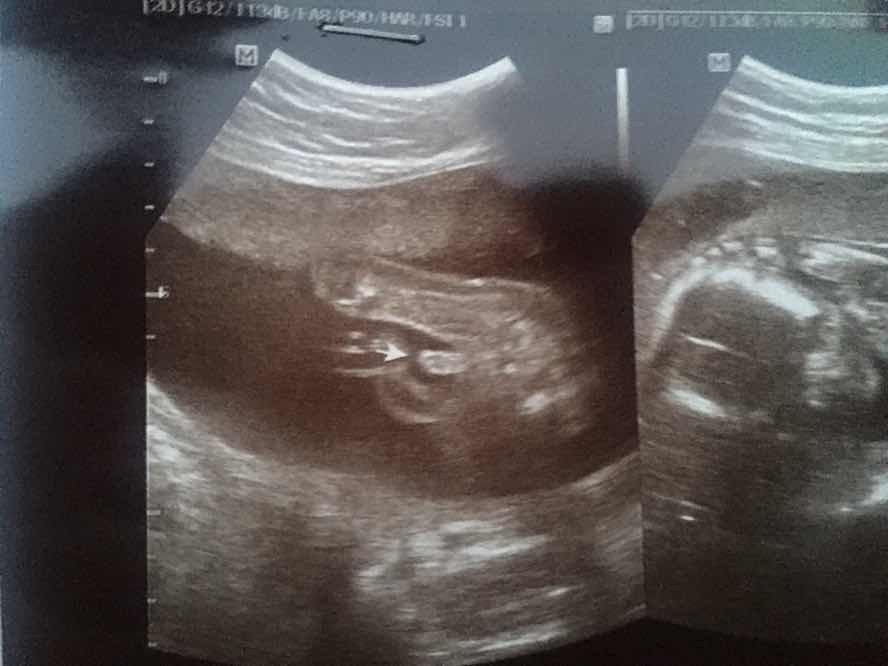

เพิ่งซาวน์มาวันนี้เลยค่ะ กำหนดคลอด 19 กค ผู้ชายค่ะ🥰🥰